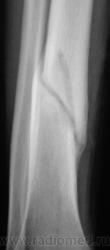

Рановато гипсик сняли, есть угроза повторного перелома.

для 2 мес даже очень хорошо, мес через полтора может уже и наступать

Консолидация хорошая.